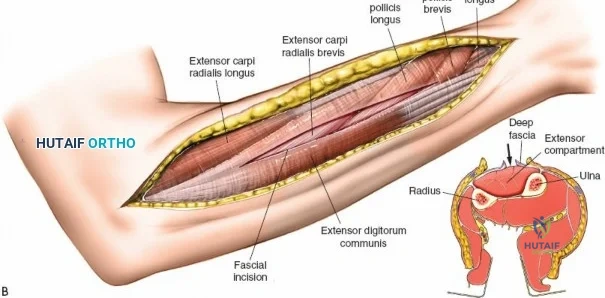

The anterior approach to the radius is an elegant example of utilizing true internervous planes to achieve deep exposure without denervating musculature. Distally, the internervous plane lies between the brachioradialis muscle (innervated by the radial nerve) and the flexor carpi radialis muscle (innervated by the median nerve). Proximally, the plane transitions to lie between the brachioradialis (radial nerve) and the pronator teres muscle (median nerve). Exploiting this plane allows the surgeon to mobilize the entire lateral muscular compartment (the "mobile wad" comprising the brachioradialis, extensor carpi radialis longus, and extensor carpi radialis brevis) away from the anterior flexor compartment.

Superficial Surgical Dissection and Internervous Plane

Incise the deep fascia of the forearm in line with the skin incision. The initial goal is to identify the medial border of the brachioradialis as it courses down the forearm. It is a common pitfall to search for this border too far laterally. At the level of the elbow, the brachioradialis is expansive and extends almost halfway across the anterior forearm. It is surprisingly easy to mistake the plane between the brachioradialis and the extensor carpi radialis longus for the correct intermuscular plane.

To confirm the correct plane, look for the superficial branch of the radial nerve. This sensory nerve runs on the undersurface of the brachioradialis muscle. Once the true medial edge of the brachioradialis is found, develop the plane between it and the pronator teres (proximally) or the flexor carpi radialis (distally). Retract the brachioradialis laterally, taking care to keep the superficial radial nerve attached to its undersurface to protect it from traction injury.